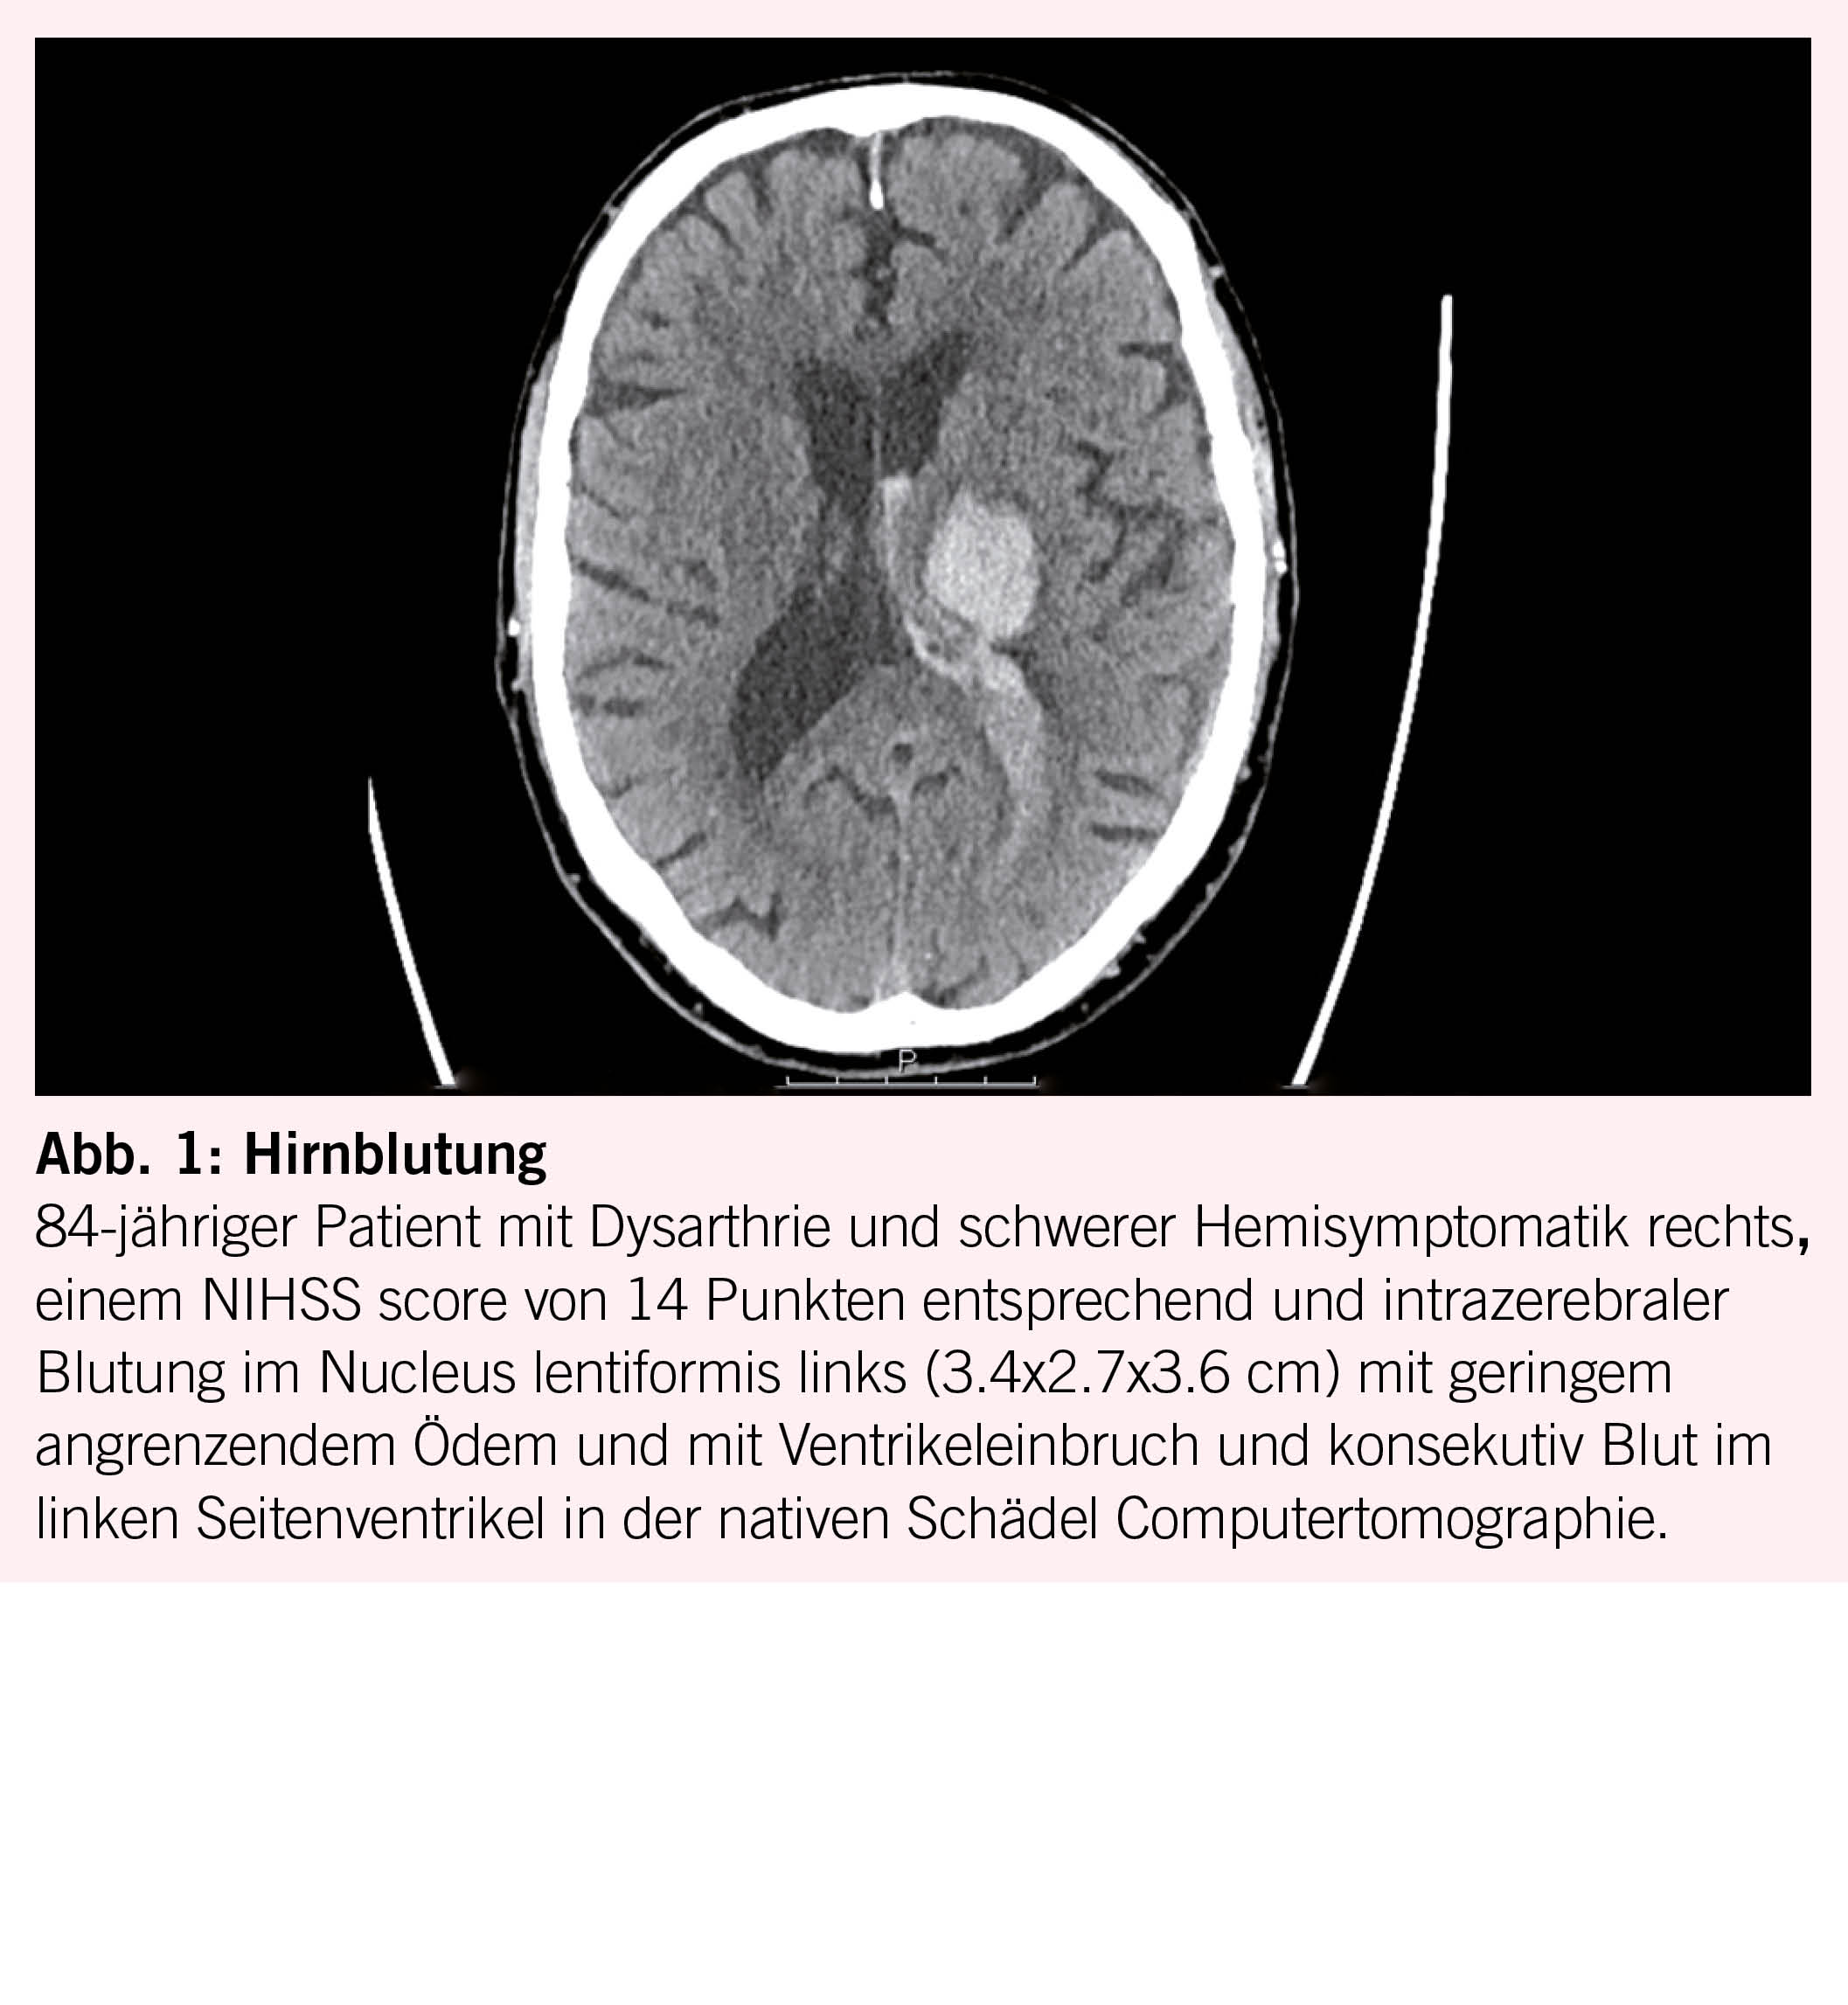

Arterielle Hypertonie verursacht einen Umbau der Gefässwand, fördert Atheromatose und Veränderungen der Endothelfunktion sowie der zerebralen Autoregulation. In der Folge entstehende Gefässrupturen führen zu Hirnblutungen (Abb. 1). Embolien, lokale Thrombusbildung oder seltener eine hämodynamische Insuffizienz verursachen Hirninfarkte (Abb. 2). Durch chronische mikroangiopathische Schäden entstehen Marklagerhyperintensitäten, Mikroinfarkte/-blutungen und neurodegenerative Prozesse wie Hirnatrophie. Es steigt nicht nur das Hirnschlag- aber auch das Demenzrisiko vom vaskulären aber auch vom Alzheimer Typ (8, 9).